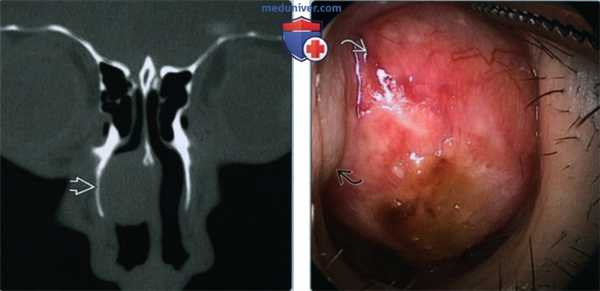

(Слева) При аксиальной КТ без КУ в полости носа слева визуализируется мягкотканное объемное образование со слегка бугристыми краями, распространяющееся в левую верхнечелюстную пазуху. Локализация образования типична для папилломы. При КТ опухоль сложно отличить от «запертого» секрета в пазухе.

(Справа) При аксиальной МРТ Т2 ВИ визуализируется неоднородная инвертированная папиллома, занимающая большую часть верхнечелюстной пазухи. Опухоль гипоинтенсивна в сравнении с секретом, «запертым» спереди и снаружи. Носовой компонент папилломы гиперинтенсивен.

2. КТ при синоназальной инвертированной папилломе:

• КТ без КУ:

о Мягкотканное образование вдоль наружной стенки носа (средний носовой ход) ± с распространением в верхнечелюстную пазуху:

- 40% содержат костные включения

- 10% содержат опухолевые кальцинаты

- Местный гиперостоз соседних костей (бляшковидный или конический) может указывать на область происхождения опухоли

о Односторонняя обструкция формирует картину воспалительного поражения пазух, обусловленную блокадой остиомеатального комплекса

о При малых ИПап могут не обнаруживаться изменения костей, что затрудняет идентификацию опухоли

о Большие ИПап вызывают ремоделирование и объемное воздействие на средний носовой ход:

- При костной деструкции ± локальной потере церебриформной морфологии предполагайте синхронный плоскоклеточный рак (ПКР)

• КТ с КУ:

о ИПап накапливает контраст, «запертое» содержимое пазухи - нет:

- Различная картина контрастного усиления: от диффузного до неоднородного

- Конволютивный, церебриформный вид при контрастировании